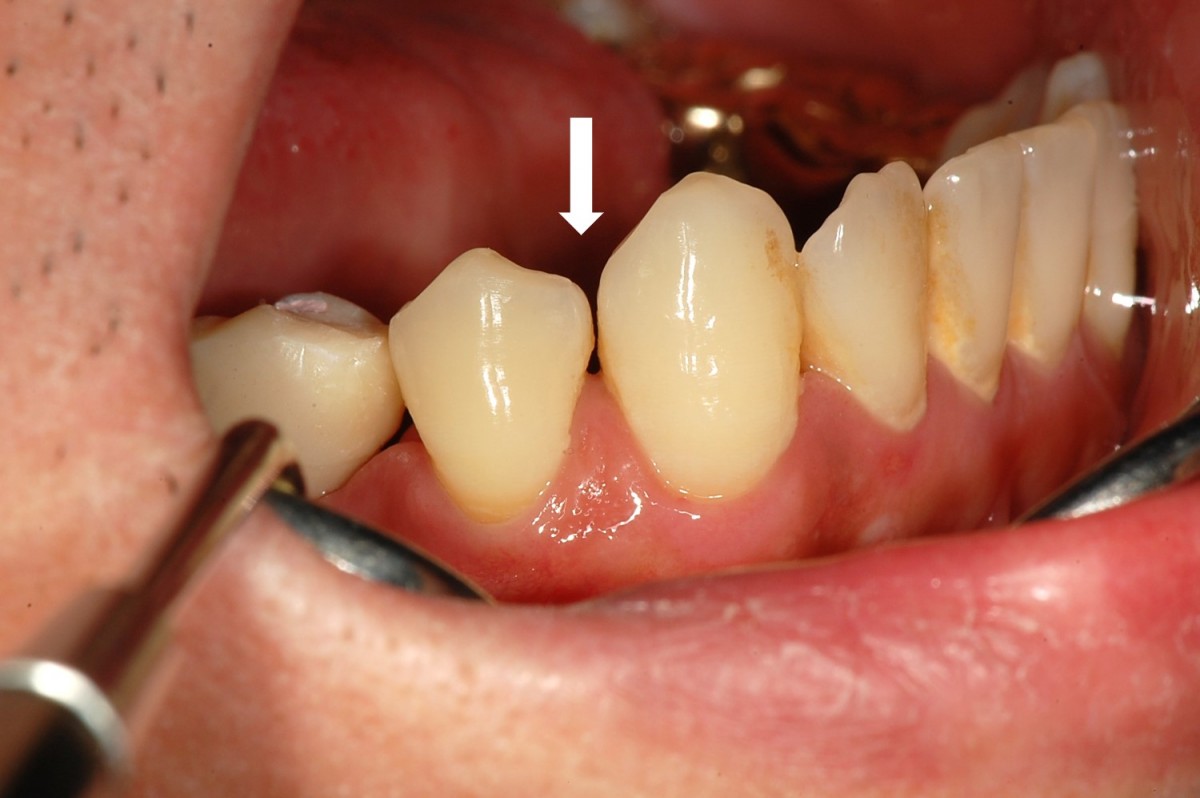

▲Remaining promary tooth